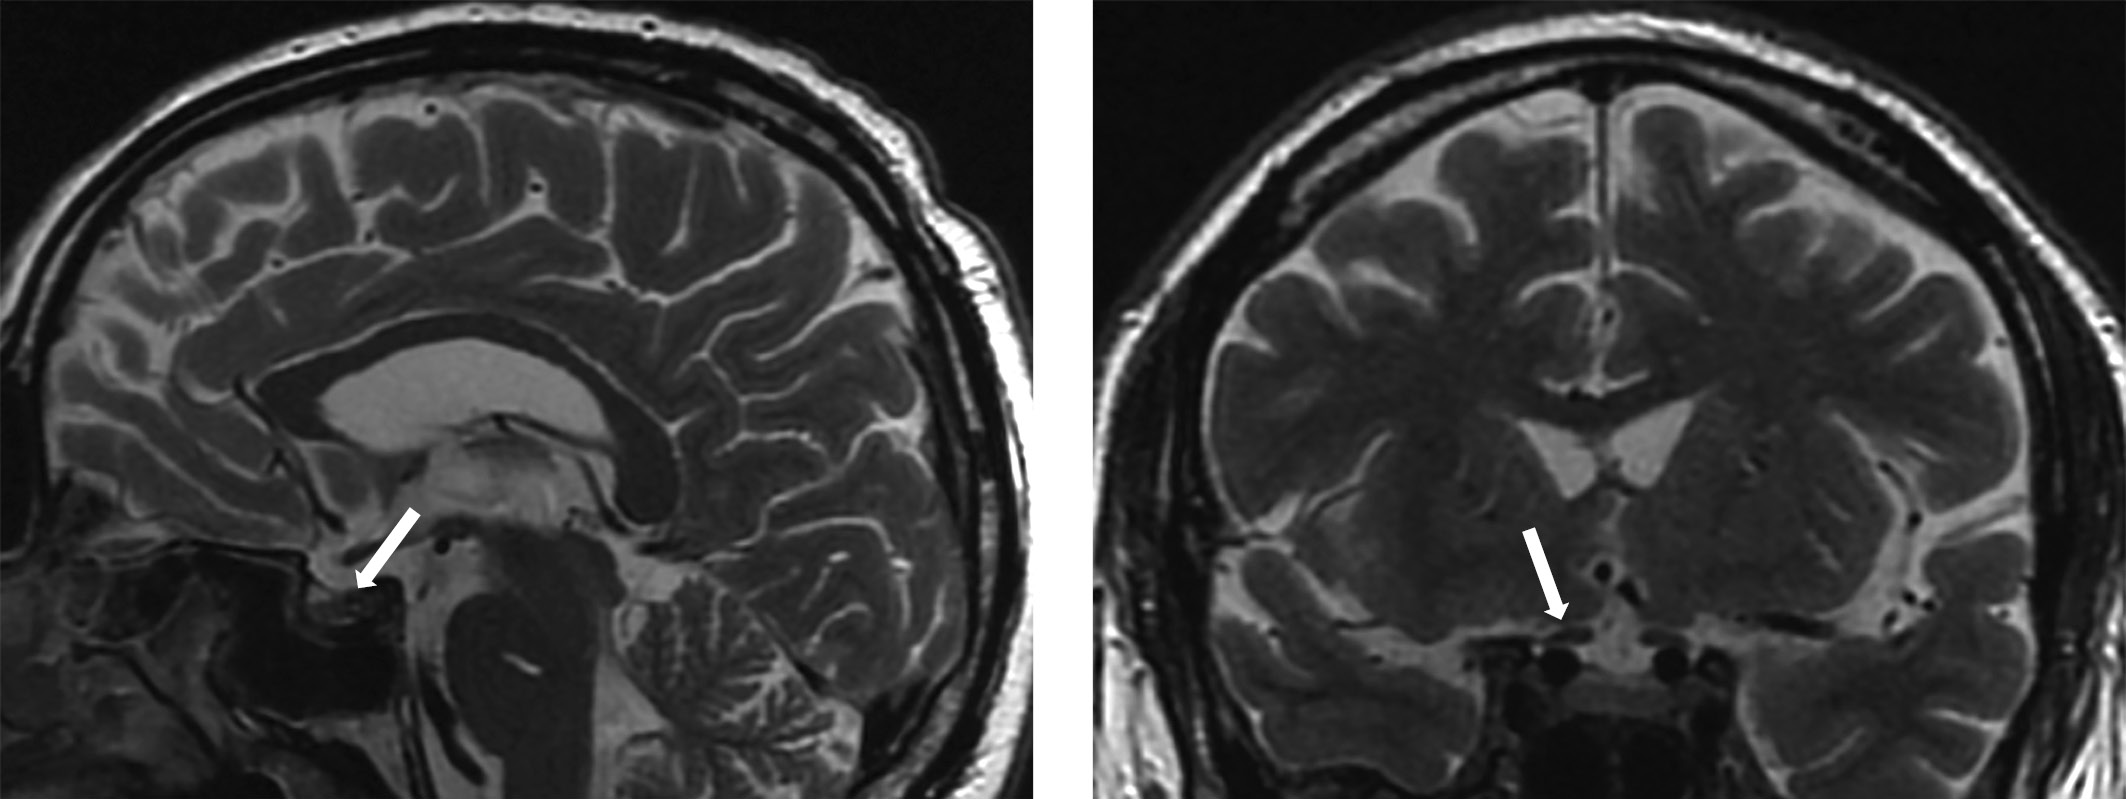

Воспалительный процесс может поражать как переднюю, так и заднюю доли гипофиза. Следовательно, в соответствии с анатомическим строением железы выделяют аденогипофизит (воспалительный процесс в передней доле гипофиза), инфундибулонейрогипофизит (воспаление воронки и задней доли гипофиза), пангипофизит (поражение всей железы) (рис. 1) [21][22].

Рисунок 1. МР-картина хиазмально-селлярной области.

Сагиттальный и фронтальный срезы.

С целью визуализации хиазмально-селлярной области нашему пациенту была выполнена МРТ.

Согласно данным исследования у пациента выявлены типичные МР-признаки гипофизита: синдром «дурального хвоста», увеличение объема гипофиза, диффузная неоднородность сигнала от ткани аденогипофиза.

МРТ-исследование не выявило опухолевых образований, однако визуализированный гипофиз деформирован, его размеры составили по вертикальному сечению — 8 мм, поперечному — 16 мм, переднезаднему — 15 мм (рис. 1). Тогда как размеры гипофиза при предыдущем исследовании были больше — 13×22×16 мм соответственно (рис. 2). Структура аденогипофиза неоднородна, в том числе за счет формирования фиброзных изменений в задней части, а при контрастном усилении отмечается выраженное неоднородное накопление контрастного вещества с наличием гиповаскулярных участков, соответствующих фиброзным изменениям. Выявлено активное накопление парамагнетика прилегающей твердой мозговой оболочкой, что соответствует синдрому «дурального хвоста». Воронка не утолщена, расположена срединно. Задняя доля гипофиза достоверно не визуализировалась.